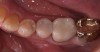

Fig 5. Preoperative view of a patient who presented with two defective amalgam restorations requiring replacement.

Figure 5

Fig 6. The amalgam restorations were thoroughly removed and the cavities prepared, after which caries indicator was applied to ensure the presence of only healthy, caries-free tooth structure.

Figure 6